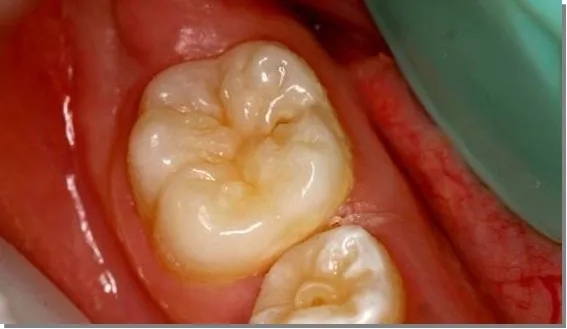

做窝沟封闭前、后